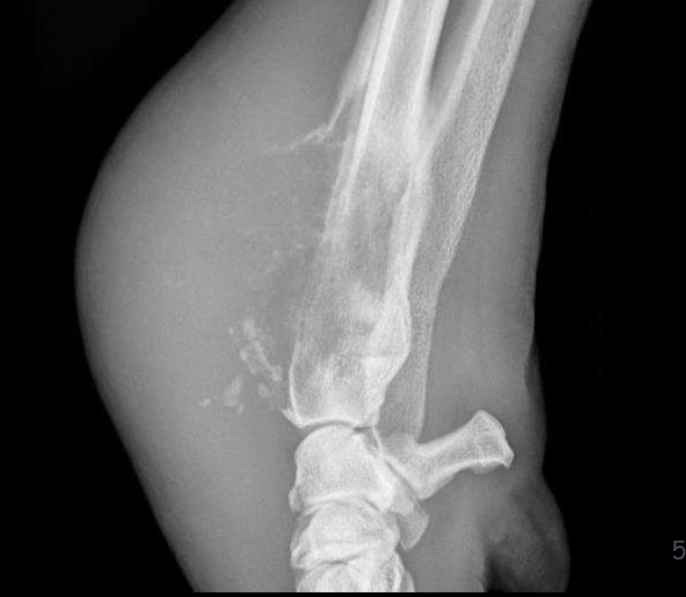

Soft tissue mineralization of the triceps at its insertion on the tuber olecrani

dystrophic

Soft tissue mineralization caudal to the ulna